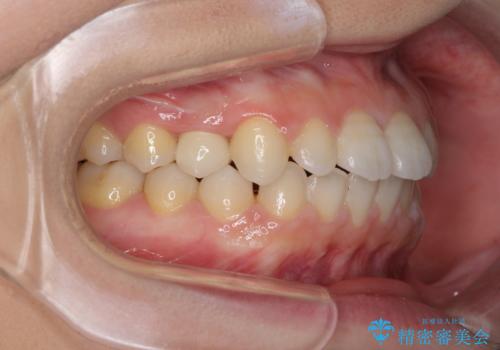

- 歯の欠損による隙間だらけの歯並びを気にして来院された患者様です。

上顎左右1本ずつ欠損していたため、歯列矯正により欠損部位にスペースを集め、その後欠損部位をインプラントにて補綴することとしました。

インビザラインによる矯正治療も提案しましたが、長時間の装着や自己管理が難しいとお考えで、ワイヤーによる矯正治療を行いました。

歯並びは比較的早めに整いましたが、インプラントを埋入するにあたって前後の歯根位置を改善する必要があり、矯正治療に期間を要することとなりました。